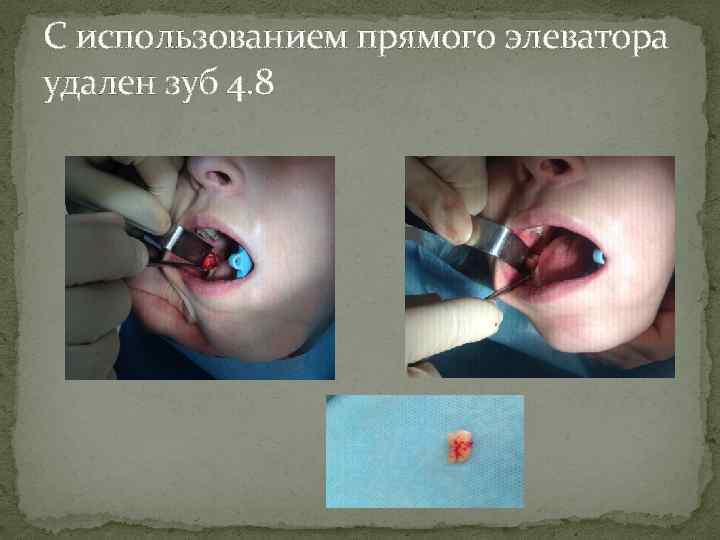

С использованием прямого элеватора удален зуб 4. 8

С использованием прямого элеватора удален зуб 4. 8